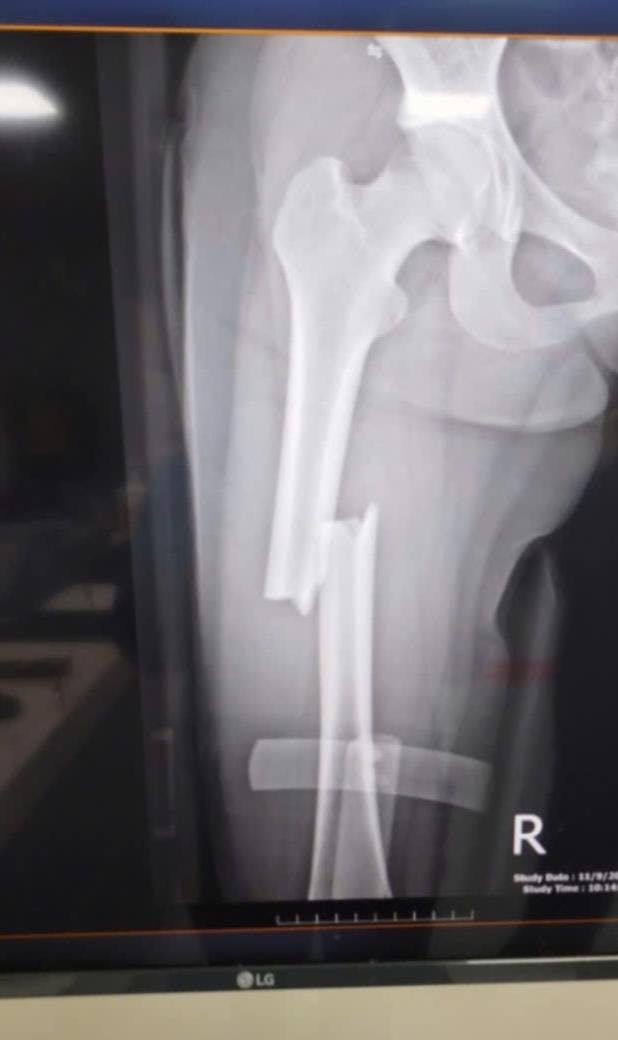

Hoai fick akut första hjälpen och fördes till sjukhuset Nghe An 115. Röntgenresultaten chockerade hans familj: Hoai hade en tredelad lårbensfraktur – en komplex skada som krävde noggrann operation och en lång återhämtningstid.

Samtidigt bröts en framtand och två andra tänder var lösa, vilket påverkade hennes dagliga liv och mentala tillstånd kraftigt. Samma eftermiddag utförde läkare en akut operation.